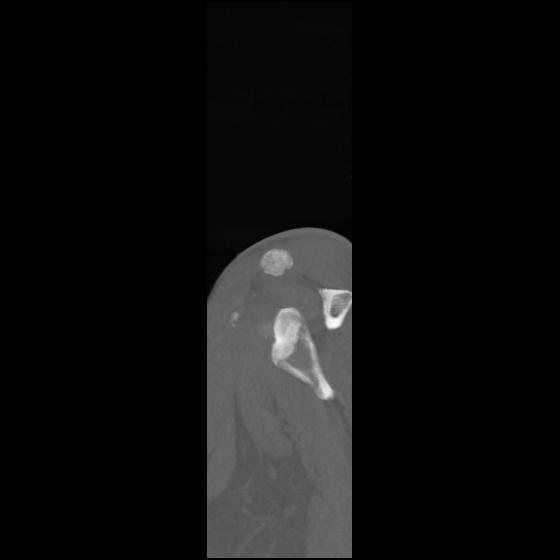

24 ANGIO,CE,Sag-MIP,5.000,ANGIO,Sag-MIP,